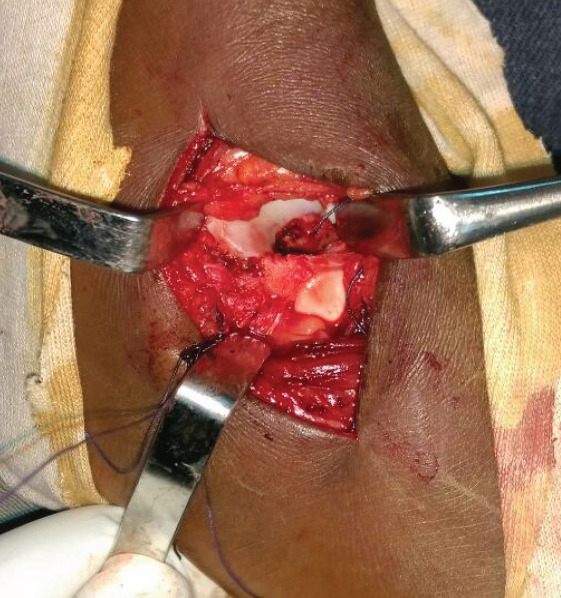

Case report: We report a case of this rare lesion managed in our department. It was a 16-year-old girl who presented with heel pain at walk, without any trauma. Radiologic explorations found a pathologic fracture of the right talus due to a bone cyst. A surgical procedure was proceeded, with curettage, and bone grafting completed by a plastered immobilization. Histopathology confirmed the diagnosis of ABC. Consolidation was achieved in 2 months, and there was no recurrence after 5 years.